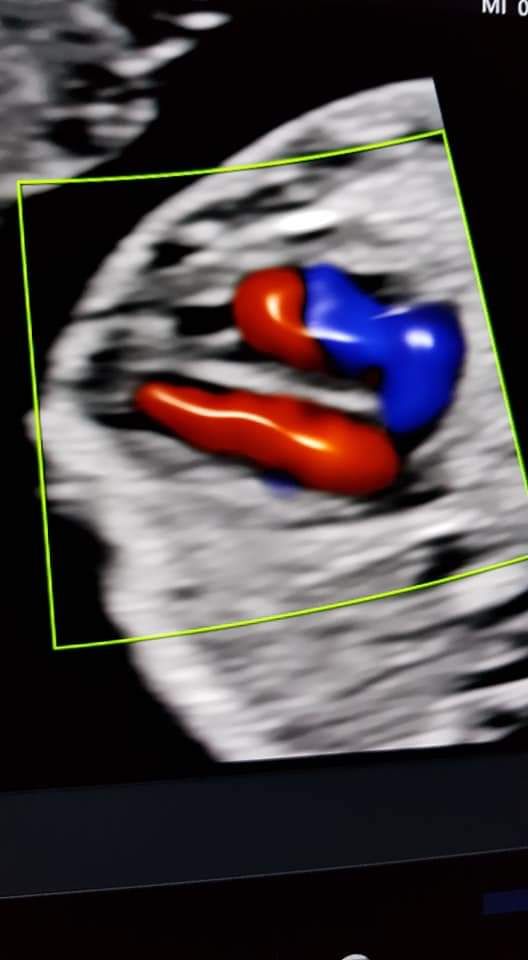

Foto e video